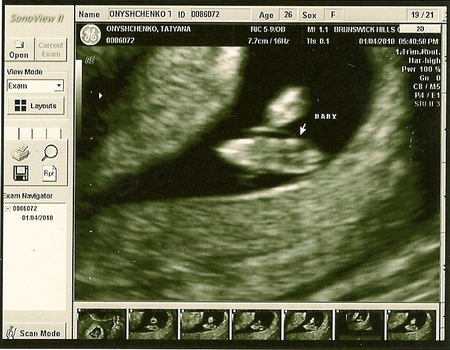

у нас оно бьется 145 ударов в минуту... врач сказал, что для 8й недельки это нормально, чем меня несказанно порадовал) Вот про размерчики я немного не поняла... где их искать, выложу фото, может кто-то знает где спрятались наши размерчики))) Поставили ПДР на 19 августа, львенка ношу)))Дали срок 7 недель и 2 дня, я в ответку пошутила- я вам даже точный час могу сказать...))) а сама держу фотографию... на ней ничего не видно..только пятнышки... но они такие родные эти пятнышки..самые-самые родные! Сказали нам, что все хорошо у нас, растем хорошо и по срокам, и чтоб продолжали так дальше)) следующий прием назначили на 21 января..анализы брать будут)

Может тут кто-то уже "бывалый" разглядит наши размерчики, уж очень интересно)) На этом откланиваюсь,девочки! Всем легкой беременности и скоростремительных родов!)